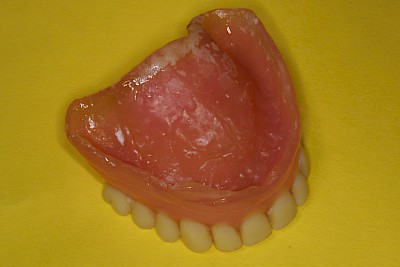

Belag

Weiche Beläge oder Speisereste sollten zunächst durch Intensivierung der Prothesenpflege beseitigt werden. Harte Beläge, die sich auch mit Zahnprothesenbürsten entfernen lassen, können durch einen Zaharzt mit speziellen Prothesenreinigungsgeräten (Ultraschallbad) entfernt werden.